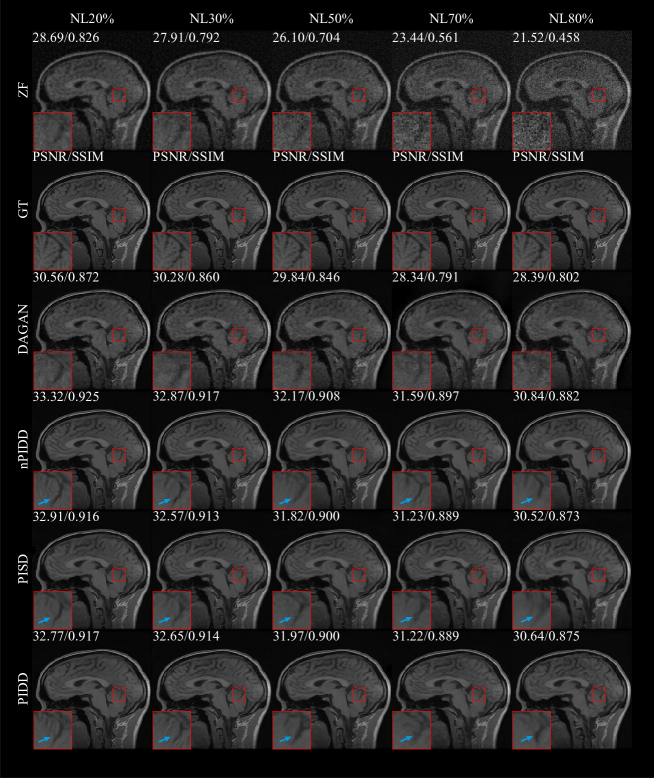

Testing examples of different methods are shown in Fig. 5. Our method is superior to other methods in terms of overall reconstruction quality and edge information reconstruction. We can see that ZF is quite blurred, mixed with many artefacts. Compared with traditional TV and L1-ESPIRiT methods, the noise reduction of ADMM and DAGAN are greatly improved, but the detailed information is still lost significantly. The reconstruction result of L1-ESPIRiT shows rich details, but it is poor in de-noising and time-consuming. Compared with PIDD and PISD, nPIDD lacks multi-channel information. Although the basic structure can be completely restored, and most noise is reduced, the excessive smoothing phenomenon is severe compared to PIDD and PISD. From the zoom-in area, it can be seen that PIDD clearly reconstructs the edge information of the brain, but this structure is very shallow in the results of PISD.

The testing examples of the reconstruction are shown in Fig. 9. It can be seen from the results that PIDD has a significant recovery effect on edge information in the case of a low downsampling percentage (10–30%). The edge information of PIDD, particularly in sulci and cerebellum areas, is greatly preserved, compared to PISD. The texture details of PIDD are also richer than nPIDD. In the case of a high downsampling percentage (40–50%), the reconstruction problem becomes simpler, and the advantages of PIDD with enhanced reconstruction of edge information and the advantages of multi-channel data are less obvious. In the experiment of Gaussian 2D 50% undersampling, PIDD, PISD and nPIDD basically have the same quality of the reconstruction.

All considered methods can restore image structure and edge information for low and medium noise levels (20–50%), with PIDD having strong advantages over PISD and nPIDD. This advantage weakens as noise level increases, and PISD, which focuses on overall information recovery, performance slightly surpasses PIDD, which focuses more on edge information preservation, for high noise (70–80%).

Experimental results verified that the proposed dual discriminator design does greatly improve reconstruction quality of edge information, particularly for sulci and cerebellum areas with rich edge information. The utilisation of multi-channel data also reduces the excessive smoothing phenomenon to a certain extent, and the texture of the tissue can be also better preserved.